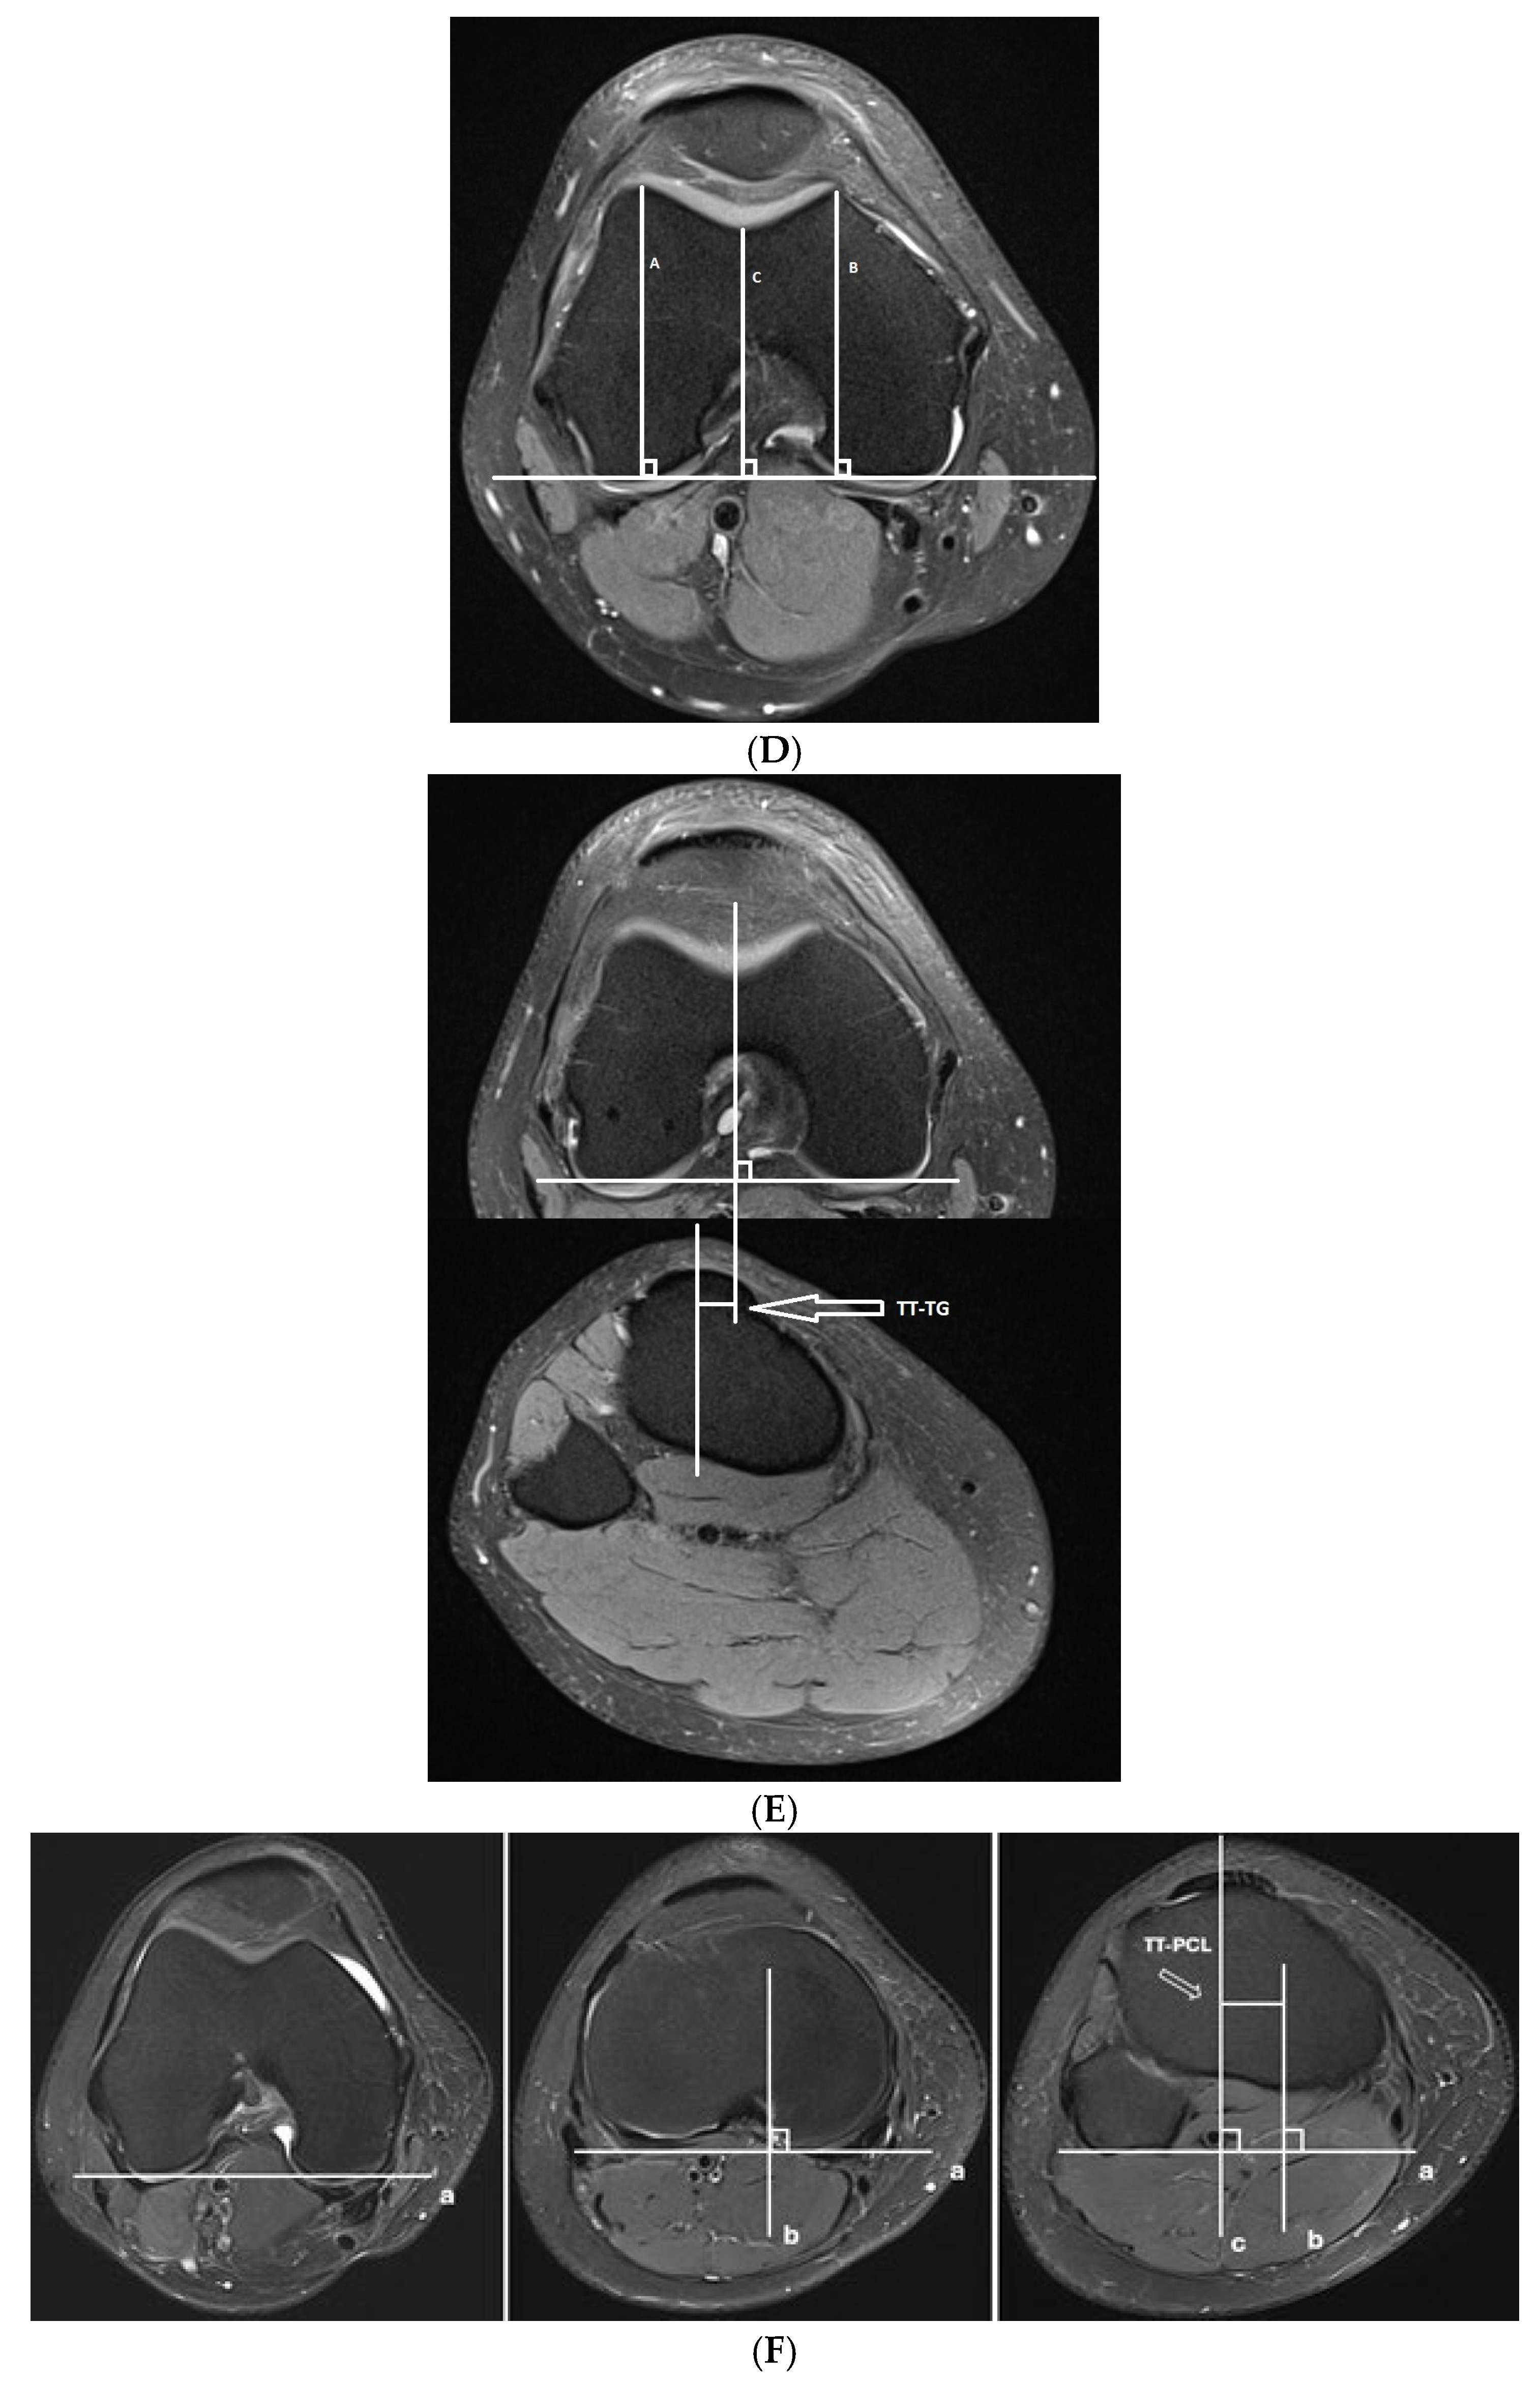

- Trochlear dysplasia measurements

- Lateralization measurements